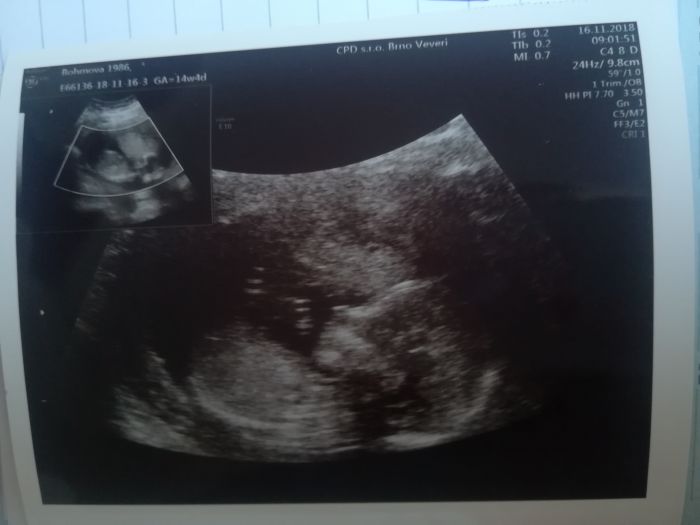

[1105746] Tak to mame Misi stejne,ja uz mam dnes taky po kontrole,mrnous na doktorku zvysoka kaslal-otoceny zadeckama dopredu a hlavou dolu si spokojene chrnel..jsme se s MUDrou hodne nasmaly-cimz se nam ho podarilo alespon trochu pootocit..

Poradna + druhy velky utz za 5 tydnu,v patek pred Vanoci a to budu taky 21tt.A MUDra si zatim porad stoji za svym,ze tam vidi cvrcka,ale priste nam to pry uz rekne na 100%..